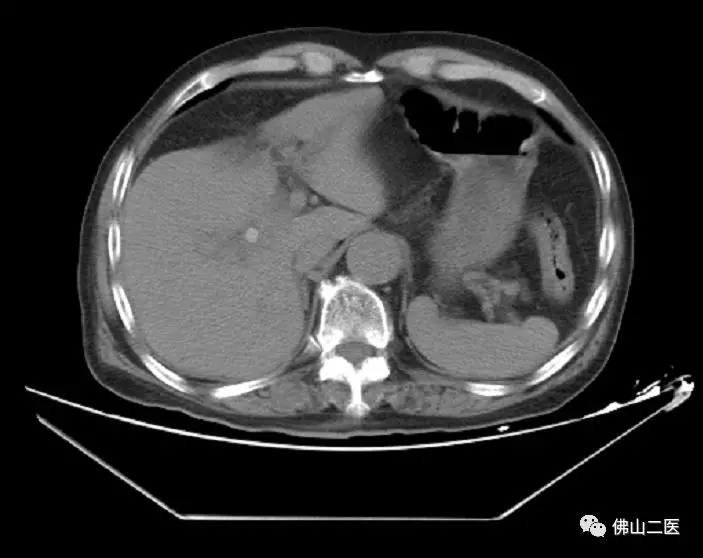

手术前实验室检查及CT影像学(箭头处)明确位于肝门部的胆管结石引起胆道梗阻并感染情况